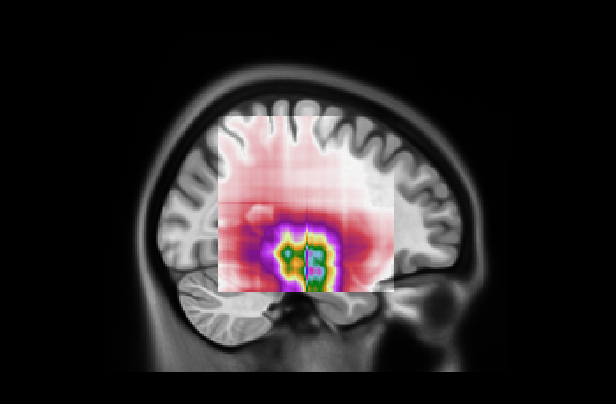

Refer to caption

Figure 7: (Left) Attention distribution for each plane averaged on all the five test to provide entire dataset distributions; (Right) Visualization of mean 3D attention map of entire dataset overlapped to MNI152 template

This subsection examines the visual results and quantitative analysis concerning the brain areas emphasized by each model. Fig. 7, on the left, displays the attentional weight distributions across the three planes, averaged over all five folds of the cross-validation. This averaging provides a comprehensive view of the data distribution across all images in the dataset. Starting from the entire dataset distributions, the 3D attentional map was created as detailed in Section 4.3. The averaged 3D map was enhanced by a factor of 10 and overlaid on the MNI152 template, which is representative of a typical patient’s brain. Combining this template with its corresponding atlas facilitates the identification of regions that, on average, received attention from the models. The right side of Fig. 7 shows the explainable MRI generated. The visual representation also indicates that the network targets the medial temporal lobe region, as suggested by the distributions. This result is confirmed by the quantitative analysis shown in Table 8, which reports the metrics for the 20 more extensive regions selected by our model and by AwareNet. As shown in Table 8(a), the three largest regions focused by our diagnosis model are the hippocampus, the parahippocampus, and the amygdala. In contrast, the 3D attentional map generated with AwareNet appears to focus on different regions. The first 3 regions highlighted are Cerebellum Gray Matter, Lateral Occipital, and Fusiform. The right part of the hippocampus appears only after them. From this result, it is also possible to note that with the same 99.9 percentile threshold for binarization, our model highlights a much more localized region. Specifically, our model selects 17 regions with a strong concentration in the top 14. On the contrary, AwareNet highlights 88 regions, 68 of which have been omitted in the Table 8.